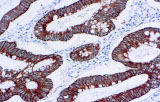

L’immunoistochimica (IHC) con anticorpi primari CE/IVD è essenziale per una diagnosi e classificazione accurata sia delle malignità ginecologiche che mammarie. Questi anticorpi consentono la rilevazione precisa di marcatori tumorali e proteine cellulari, supportando la diagnosi differenziale e guidando strategie terapeutiche personalizzate.

Studi recenti sottolineano il valore diagnostico delle proteine del complesso SWI/SNF, in particolare ARID1B, nell’identificazione di malignità ginecologiche dedifferenziate e indifferenziate – tumori aggressivi con prognosi sfavorevole. L’IHC di ARID1B offre alta specificità e viene sempre più integrata nei pannelli diagnostici per migliorare la precisione. Pannelli con marcatori aggiuntivi supportano anche la differenziazione dei sarcomi uterini, aumentando l’accuratezza diagnostica. Evidenze emergenti suggeriscono che ARID1B potrebbe rappresentare un potenziale bersaglio terapeutico nel carcinoma ovarico a cellule chiare, sebbene le applicazioni cliniche rimangano in fase di ricerca.